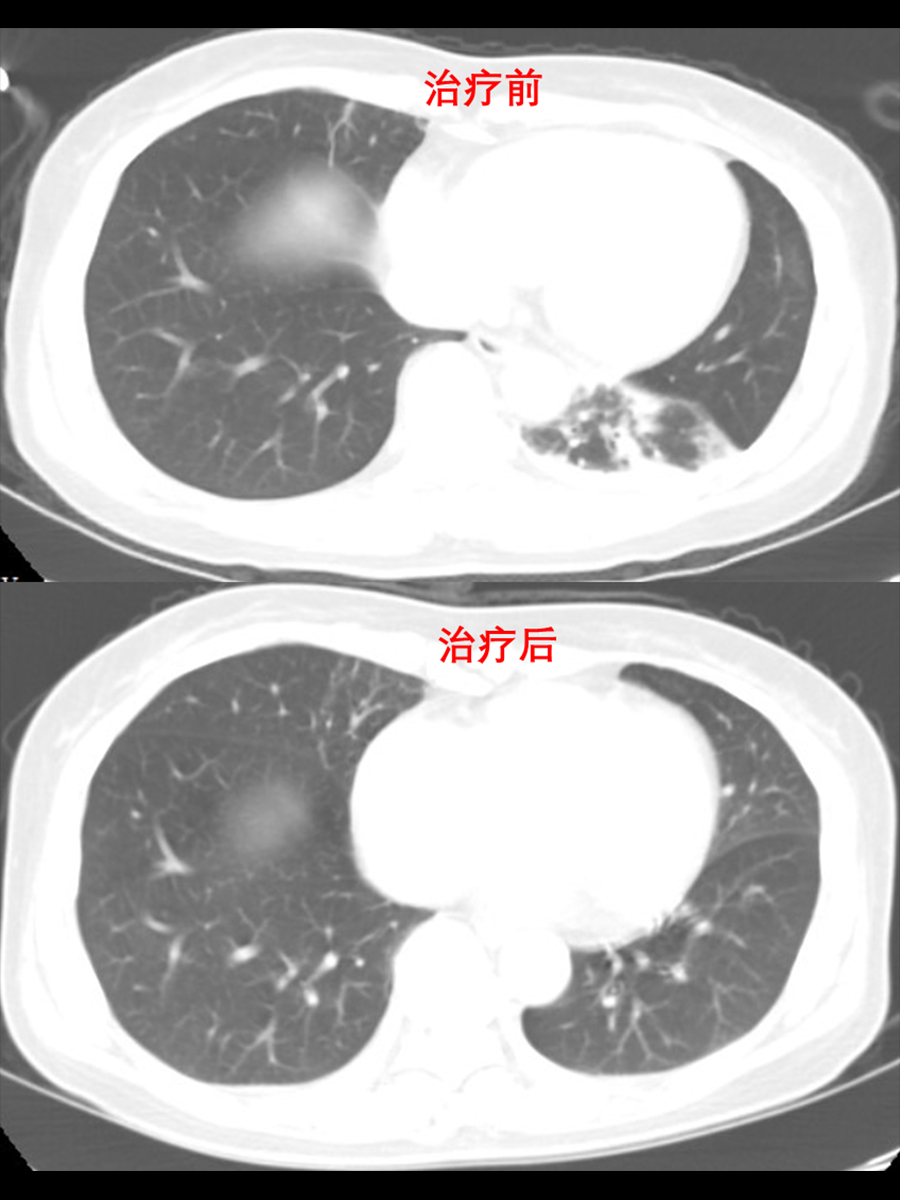

患者经积极抗感染+化痰药物治疗10天后,复查血常规提示:炎症指标完全恢复正常,复查胸部CT提示:肺部感染性病变明显吸收好转。听诊双肺呼吸音清,未闻及干湿性啰音,患者症状完全缓解出院。综上,患者症状完全缓解,各项指标恢复正常,治疗效果良好,患者顺利出院。出院后,嘱患者院外注意休息,避免劳累受凉感冒,加强营养,增强体质,呼吸内科门诊随诊。

(治疗前后胸部CT对比)